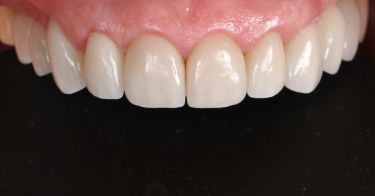

Wykonana praca protetyczna:

- licówki pełnoceramiczne na zębach górnych przednich

- korony pełnoceramiczne na zębach własnych w łuku górnym i dolnym

- korony na implanatch